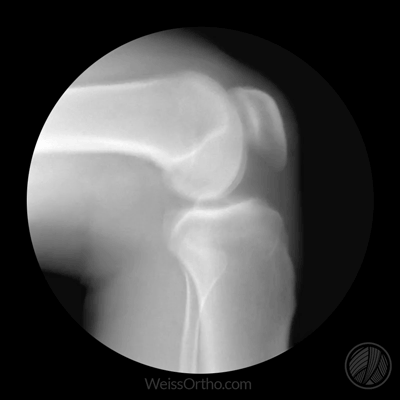

- L'objectif principal de la radiographie est de déterminer si le patient présente un rétrécissement important de l'espace articulaireLa principale raison de ce rétrécissement est que le cartilage s'est considérablement aminci et que l'espace articulaire naturel est plus étroit. En outre, nous pouvons très bien juger les articulations des personnes âgées à l'aide de radiographies.S'il y a une formation osseuse importante (ostéophytes)qui se forment spécifiquement dans telle ou telle partie du corps, les fonctions qu'elles peuvent affecter chez les personnes âgées, et lesLa formation d'ostéoïdes et le rétrécissement de l'espace articulaire sont les changements les plus classiques de l'arthrose.。

- 而L'objectif principal de l'IRM est de déterminer le degré d'usure du cartilage dans les articulations des personnes âgées, la présence de liquide dans les articulations, la quantité de liquide et l'usure du ménisque dans les articulations.Le test est souvent effectué par un médecin. Souvent, les personnes âgées dont les symptômes ne sont pas particulièrement graves et dont les déformations articulaires ne sont pas particulièrement évidentes se prêtent mieux à ce test, mais il va de soi que les personnes qui en ont la possibilité devraient subir les deux tests.